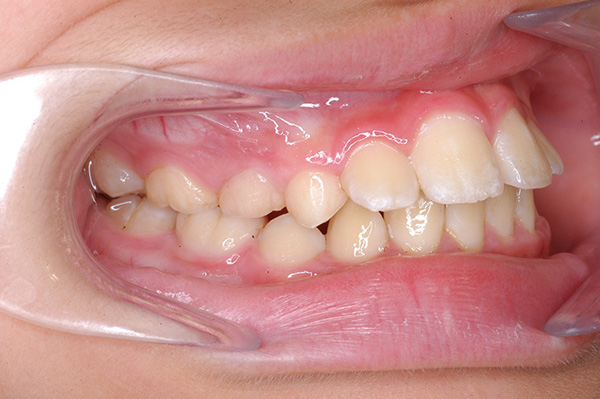

| 口腔内所見 | over jet 5.5mm,over bite 5.0mm,大臼歯関係はⅠ級 、Hellmanのdental ageはⅢBであり上突歯列を呈していた。 |

| パノラマ所見 | 上顎左右側犬歯は近心傾斜し側切歯歯根に重なるように認められた。 |